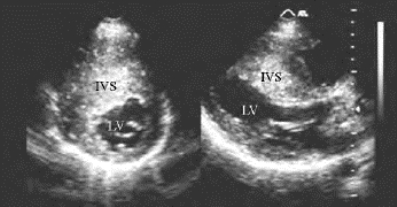

1.14.2第二节 二维超声心动图检查、测量方法及正常值

1.14.2.2二、常用切面图及用途